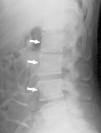

In imaging studies, in addition to marked bone sclerosis, her spine showed the presence of lines parallel to the cortex of the vertebral bodies giving rise to an image of a small copy of the vertebral body within the body, a sign called “bone within a bone” (Figs. 1–3). This sign was evident in several vertebral bodies. Morphometric vertebral deformities showed no calcification of paraspinal ligaments.